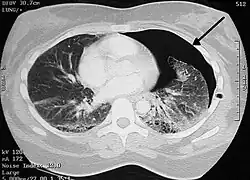

Pneumotórax do lado esquerdo (no lado direito da imagem) em tomografia computadorizada do peito. Um tubo peitoral está colocado no lado do peito, a sua luz (preto) pode ser vista adjacente à cavidade pleural (preto) e costelas (branco). O coração pode ser visto no centro.